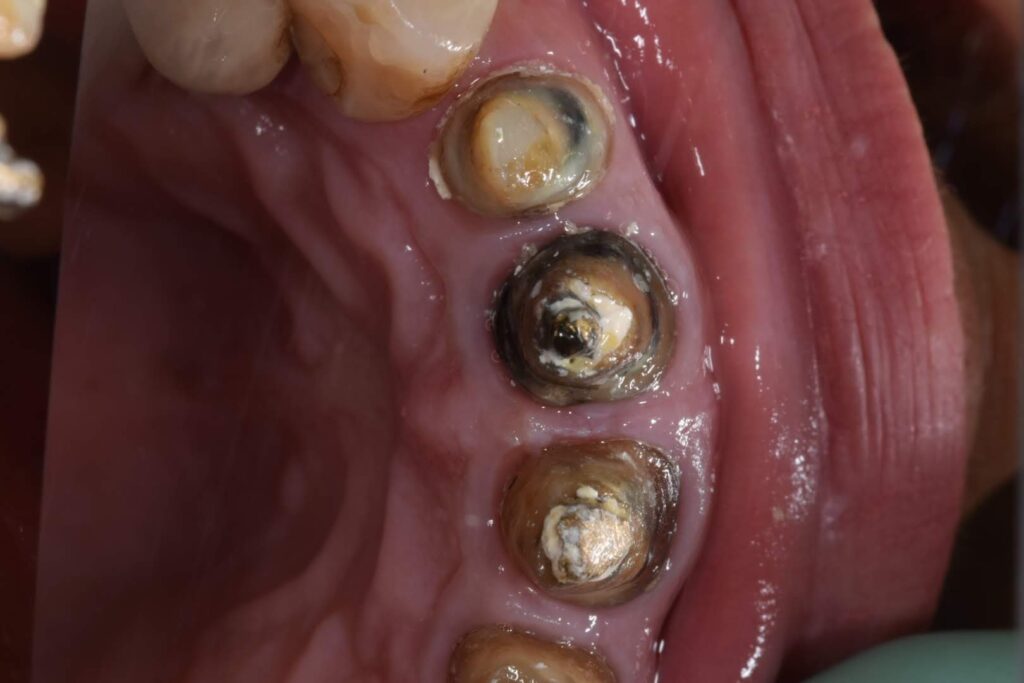

Caso clinico – ritrattamento ortogrado con apical plug in MTA